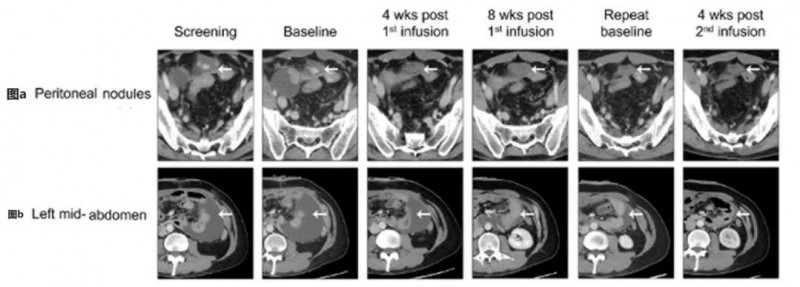

CT041治疗晚期胃癌:肿瘤病灶及腹水均改善 胃癌

胃癌CT041治疗晚期胃癌:肿瘤病灶及腹水均改善

CT041治疗晚期胃癌:肿瘤病灶及腹水均改善Claudin18.2(CLDN18.2)是一种高度选择性的细胞表面分子,属于泛肿瘤靶点,在多种上皮肿瘤(尤其是胃癌、胰腺癌)中均有表达,该靶点在正常胃组织中表达有限,但在原发性胃癌及其转移灶中表达显著增高。我国研究人员基于此,研发了首款靶向Claudin18.2的CAR-T细胞产品——CT041。据悉,CT041